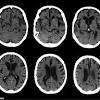

Study: Alzheimer's pathology might be transmittable via medical procedures A new study suggests that the precursor of an abnormal protein that triggers Alzheimer's disease could perhaps be transmitted from person to person through the transfer of tissue or certain specialized medical or surgical procedures, its authors said.

'Seeds' of Alzheimer's disease may have spread in banned medical procedure British scientists have found evidence that the biological seeds of Alzheimer's disease could be passed on through medical procedures.

Alzheimer's 'seeds' might be transferred SEEDS of Alzheimer's disease can potentially attach to surgical instruments and be transferred from one person to another during certain medical procedures, a study suggests.